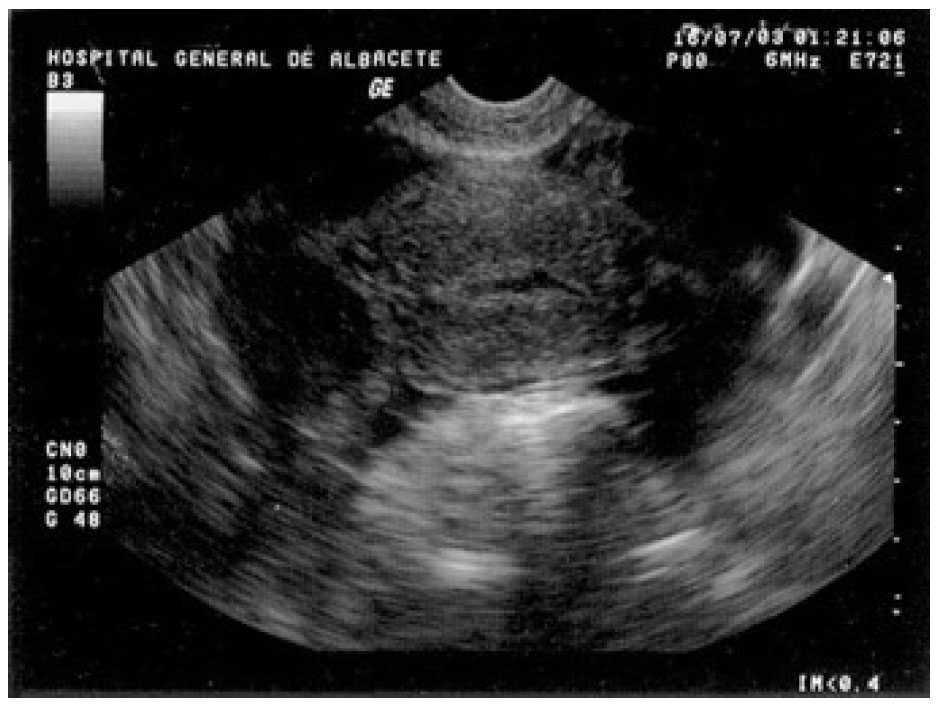

A la exploración presentaba una presión arterial de 90/55 mmHg y una temperatura de 37 °C; el abdomen era blando y depresible, con dolor a la palpación profunda en el hipogastrio y ambas fosas ilíacas, sin signos de irritación peritoneal. La movilización cervical no era dolorosa y el útero y los anejos no fueron delimitables por defensa de la paciente. En la analítica destacó una hemoglobina de 10,2 g/dl y un hematocrito del 30,6%; el resto del hemograma, las pruebas de coagulación y la bioquímica resultaron normales. La ecografía vaginal mostró un útero en anteflexión, de tamaño normal, con un endometrio lineal y una pequeña cavidad real, sin estructuras gestacionales en su interior y rodeado por una moderada cantidad de líquido libre y coágulos (fig. 1). Ambos ovarios eran normales y por encima del derecho se visualizaba una imagen redondeada, heterogénea, de 22,7 × 22 mm de diámetro (fig. 2), que se observó también en la ecografía ginecológica abdominal previa.

Figura 1. Ecografía transvaginal en la que podemos observar un útero vacío, sin estructuras gestacionales, rodeado por una moderada cantidad de líquido libre y coágulos.